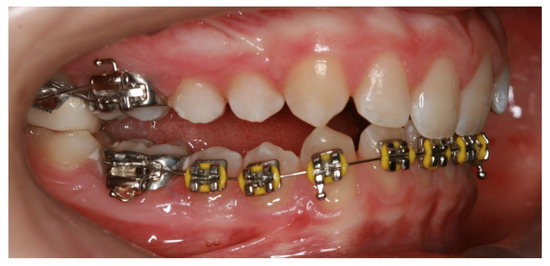

Inclusion criteria were growing patients with bilateral Class II malocclusion (ANB > 4°) due to mandibular retrognathia (SNB < 78°) with overjet (>4 mm) and deep bite (>4 mm), with no previous orthodontic treatment. Patients with developmental syndromes and anomalies (alveolar cleft and/or palate), mandibular fracture or deformities were also excluded from the study. A Class II malocclusion due to retrognathic mandible was identified through cephalographic analysis, so before-treatment (T0) and after-treatment (T1) lateral cephalograms (LC) were mandatory for all the patients. All lateral cephalograms (LC) were taken using the same equipment (Planmeca Promax, Helsinki, Finland) by an experienced dental radiology engineer under standard conditions: subjects were in the standing position and adequately protected, the Frankfort horizontal plane parallel to the floor, with the teeth in the maximal intercuspation (centric occlusion) and relaxed lips and tongue and with identical distances for each patient from the focus to the median sagittal plane of the subject’s head and to the film. Cephalometric analysis was performed for each patient before (T0) and after (T1) treatment. Definitions of the used (clinically important) angular and linear measurements are described and shown in Figure 1 and Figure 2. The linear and angular measurements were measured to the nearest of 0.1 mm and 0.1 degrees, respectively. Only the data with statistically significant changes before and after treatment are presented.

Legends: 1: U1/PP (°) is the angle formed between the maxillary central incisor (U1) long axis and the palatal plane (PP) and indicates maxillary incisor inclination; 2: U1/Y axis (mm) is the distance between the incisal edge of maxillary central incisor perpendicular to the Y axis (formed by dropping a line from the sella perpendicular to the SN line) indicates horizontal maxillary incisor distance; 3: L1/MP (°) is the angle formed between the mandibular central incisor (L1) long axis and the mandible plane (MP) and indicates mandibular incisor inclination; 4: L1/S axis (mm) is the distance between the incisal edge of the mandibular central incisor perpendicular to the S axis (formed by dropping a line through the posterior conture of symphysis perpendicular to the MP line) and indicates horizontal mandibular incisor distance to S axis; 5: L6/MP (°) is the angle between the mandibular first molar (L6) long axis (line passing through the mesial cusp tip and the mesial root tip) and the mandibular plane, and indicates mandibular first molar inclination; 6: L6/MP (mm) is the distance between the mesial cusp tip of the mandibular first molar perpendicular to the mandibular plane and indicates vertical mandibular first molar distance; 7: overjet is the horizontal distance from the maxillary incisor tip to the labial surface of the mandibular incisor; 8: overbite is the vertical distance from the mandibular incisor tip to the maxillary incisor tip; 9: U1/E line is the horizontal distance from the labial surface of the maxillary incisor perpendicular to the E line.

Figure 2. The angular and linear dentoalveolar measurements.